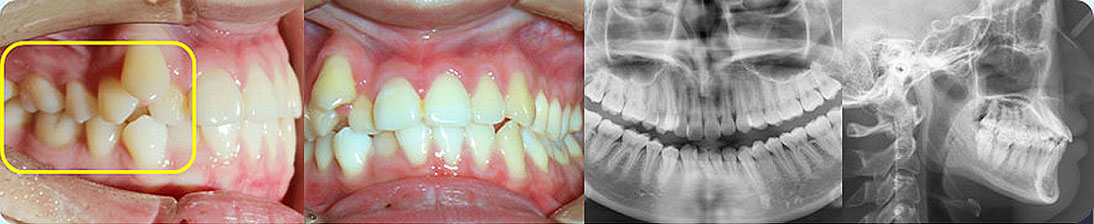

- 【診斷】

先天缺少下切牙2顆

上前牙錯(cuò)位于下前牙后側(cè),前牙無咬合功能,上牙槽及上唇后縮

打造醫(yī)生:德倫口腔正畸中心鄧毅醫(yī)生

- 【治療方案】

調(diào)整弓形及配合Ⅲ類牽引,實(shí)現(xiàn)頜跳躍

矯治前后對(duì)比

牙列整平排齊,前牙內(nèi)收;覆蓋、覆合正常;尖牙和磨牙達(dá)到中性關(guān)系;上下中線對(duì)齊;下頜后縮改善